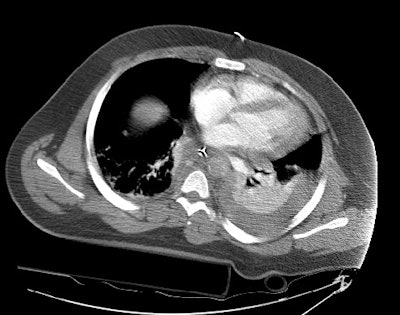

CT images more inferiorly revealed an intimal flap and marked irregularity to the contour of the aorta consistent with traumatic injury (black arrows). Slightly below this level there was a near complete lack of opacification of the vessel (lower image).